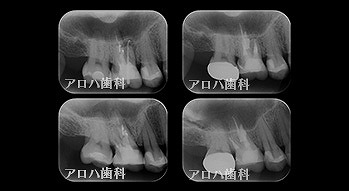

case10

左上に腫脹、圧痛

根尖部に透過像

術前、術直後、予後

術前、術後